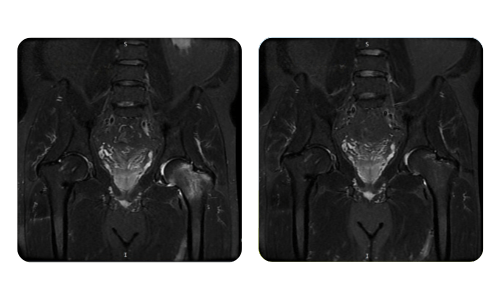

I progressi dei nostri pazienti, misurati prima e dopo la terapia iperbarica, riflettono l'efficacia e l'impatto positivo del trattamento. Scopri i risultati documentati della terapia iperbarica presso la clinica Hyperbarium Oradea, basati su valutazioni cliniche e dati oggettivi che evidenziano miglioramenti significativi in diverse condizioni.